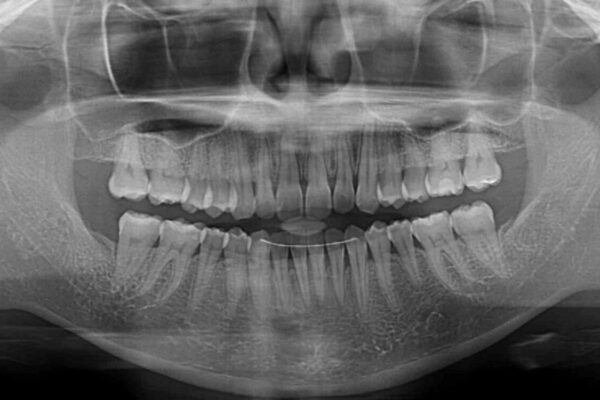

前歯のデコボコで前方に出ていることを気にして来院された患者様です。

上顎前歯が捻れて前方に飛び出しており、下顎前歯もそれに沿うようにデコボコとなっていました。

IPR(歯と歯の間を削る処置)によりスペースを獲得して上下顎前歯のデコボコを改善し、飛び出している前歯が引っ込むように設定し、インビザラインにて矯正治療を行うこととしました。

• 【モニター】前歯のデコボコをインビザラインで改善 治療前画像